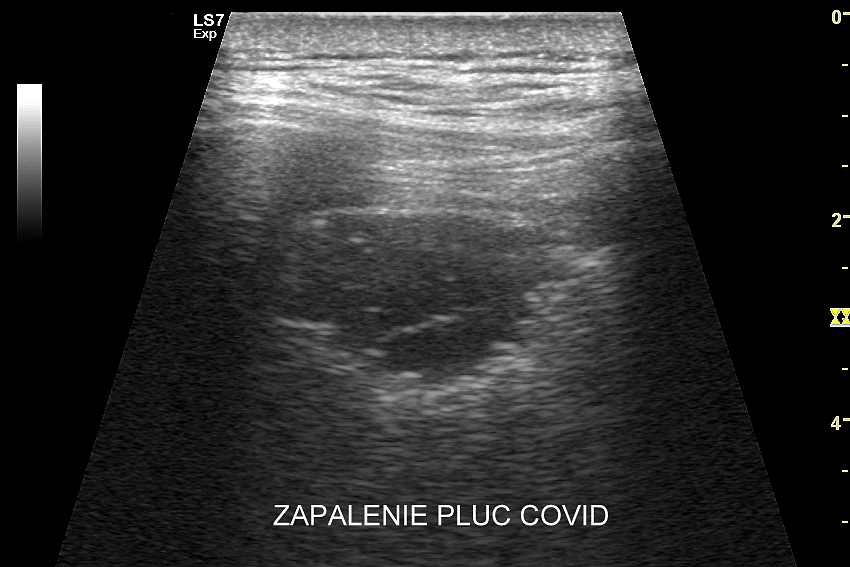

Ultrasonografia płuc oparta jest o fizykę fal akustycznych. Wychwytuje zarówno schorzenia lokalizujące się w zewnętrznych partiach płuc oraz w jamach opłucnowych w postaci realnego obrazu, ale także wykazuje istotne diagnostycznie informacje z głębszych partii narządu na podstawie specyficznych artefaktów generowanych przez patologie wewnątrz płuca.

Kluczem do wartościowego zastosowania metody USG w diagnostyce pulmonologicznej jest zrozumienie jej możliwości oraz ograniczeń. USG jest niezwykle czułym badaniem w diagnostyce zapaleń płuc zarówno płatowych, jak i atypowych, np. wywołanych przez Mycoplasma lub Chlamydia. W przypadku zapalenia płuc pojawienie się widocznych zmian sonograficznych wyprzedza wystąpienie fenomenów osłuchowych wykrywanych przy osłuchiwaniu klasycznym stetoskopem. Metoda USG jest również bardzo czuła w diagnostyce chorób opłucnej i jam opłucnowych, takich jak nowotwory opłucnej, odma odma opłucnowa czy płyn w jamie opłucnowej. W rękach doświadczonego lekarza badanie USG może być przydatne w wykryciu zatorowości płucnej, a nawet guzów nowotworowych płuc.